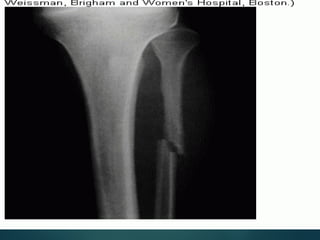

Healing

is a continous process – 3 stages:

 Organization of hematoma which result in soft

organizing procallus.

 Conversion of the procallus to

fibrocartilagenous callus which give effective

immobilization of the bone fragments.

 Replacement of the fibrocartilagenous callus

by osseous callus which remodel along the line

of wt. bearing to complete repair.

In this region of a recent fracture, callus is seen forming at

the broken ends of bony trabeculae that extend to the

center from the left and top.

Healing……

 Immediately after the fracture, hematoma fills the

fracture site, seals off the fracture and provide

framework ingrowth of fibroblast and capillary &

give anchorage to the bone fragments.

 The platelets degranulate, inflammatory cells

migrate, PDGF, TGF-B, FGF, IL-s, are released, all

activate the osteoprogenitor cells in periosteum,

medullary cavity and surrounding soft tissue and

stimulate osteoclastic and osteoblastic activity.

 At the end of the first week, the hematoma

organizes, a fusiform uncalcified tissue procallus

forms & provides the anchorage between the

two fractures ends but no structural rigidity

provided.

 Osteoprogenitor cells deposits trabecular of

woven bone in subperiosteal and in the

medullary cavity, the mesenchymal cells in soft

tissue differentiate into chondroblasts and

fibrocartilage and hyaline cartilage envelop the

fracture site.

 The repair is maxim. in 2-3 weeks and this

fibrocartilagenous callous stabilize the fracture

site.

 The cartilage undergoes enchondral

ossification, the fibrocartilagenous callus

replaced by osseous callus which mineralizes

and remodel along the line of weight bearing

to complete repair.

 The callus excess is resorbed and the callus

reduced in size and shape until the outline of

the fracture is reestablished.

In this regionof a recent fracture, callus is seen forming at the broken ends of bony trabeculae that extend to the center from the left and top.